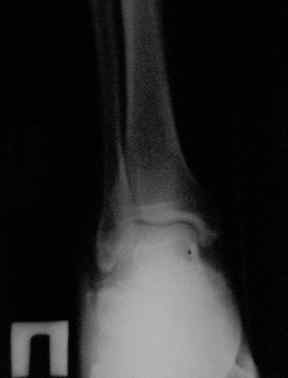

Отправляю снимки(свежие)и фото стоп.

С уважениемД.Б.

С левой стопой дело похуже. Нужен прямой снимок, да и боковой не помешает повторить на всю стопу, ну и плюс аксиальный. Готовтье аппарат.